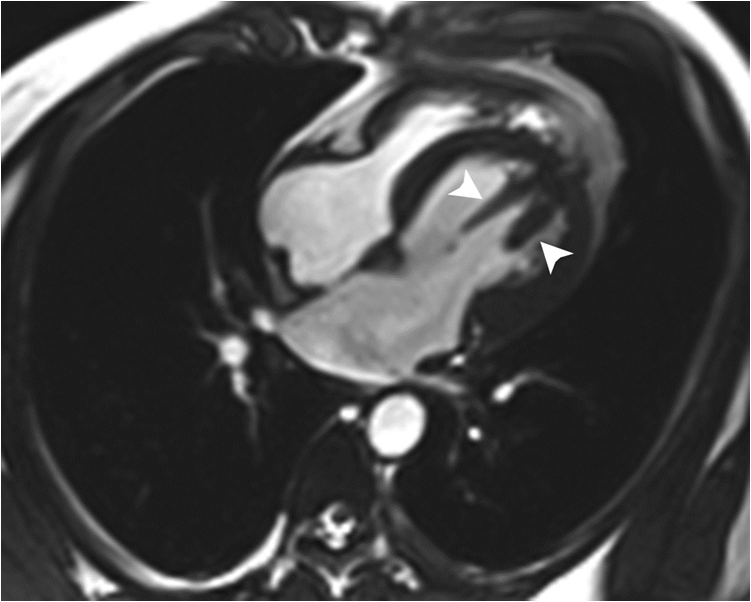

19 / M, Chief complaint: Recurrent episode of chest pain and cardiac enzyme elevation with normal coronary angiography, family history of sudden cardiac arrest

Jinwoo Son, Severance Hospital, Yonsei University College of Medicine